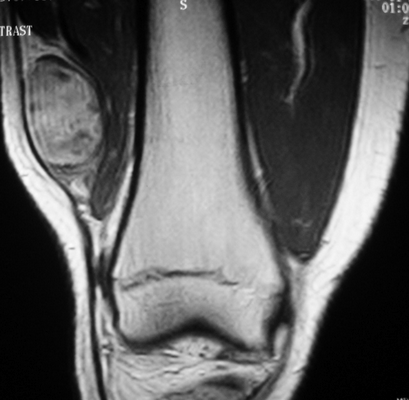

Саркома мягких тканей бедра на МРТ

УЗИ мягких тканей бедра и голени

Ультрасонографию нижних конечностей в большинстве случаев рекомендуют пациентам с подозрением на травматические повреждения и инфекционно-воспалительные процессы. Также УЗИ применяют в комплексной диагностике злокачественных опухолей, локализующихся не только в длинных трубчатых костях обсуждаемой области, но и в прилежащих мягких тканях.

В большинстве случаев здесь выявляют саркомы - агрессивно текущие, склонные к развитию рецидивов и метастазированию новообразования. Указанные особенности делают крайне важным своевременное установление онкологического диагноза и назначение комплексного лечения.